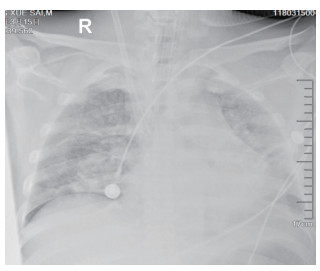

该患者入院后因氧合不能维持、呼吸窘迫直接从急诊收治ICU,大剂量激素冲击及气管插管,呼吸机SIMV+PS模式支持治疗,氧合指数改善不明显,及时行俯卧位通气,但氧合指数仍然小于100,PAO2 38 mmHg, SpO2 78%左右,考虑患者病情危重,且血流动力学不稳,血管活性药剂量大,当天下午行V-V模式ECMO治疗(右侧颈静脉-右侧股静脉),血流速度3.5 L/min,氧流量3.5 L/min,氧体积分数50%,行保护性机械通气,通气模式是压力控制(PC 15 cmH2O,PEEP 8 cmH2O,FiO2 50%,f 12次/min), 镇痛镇静,RASS评分在-4~-5分,必要时阿曲库铵静脉推注行肌肉松弛治疗。其他治疗:甲强龙500 mg治疗3 d,然后逐渐减量;乙酰半胱氨酸抗氧化、化痰、CRRT等支持治疗。ECMO治疗后生命体征明显改善,治疗第2天,血管活性药逐渐减量。治疗3 d后,循环稳定,停用血管活性药,床旁胸片提示:两肺弥漫渗出性改变,较前明显好转。患者症状好转,调节ECMO参数:血流速3 L/min,气体流速3 L/min,氧体积分数35%,控制SpO2 95%~100%之间。在ECMO治疗期间根据血流动力学和血气分析结果不断调整ECMO参数,在ECMO治疗5 d后,脱离ECMO,通气模式改为SIMV+PSV并过渡到PSV(PS 16 cmH2O,PEEP 5 cmH2O,FiO2 30%),氧合良好,在脱离ECMO 2 d后停呼吸机,停机1 d后拔除气管插管。行胸部CT检查示:两肺散在炎性病变,双侧胸膜腔积液(图 3),床旁胸片提示两肺炎性病变(图 4),两肺弥漫性渗出明显改善。后经1周治疗,查胸部CT示:右肺中下叶及左肺少许慢性炎性改变(图 5),病情稳定转至呼吸科病房。

| 图 4 3月19日胸部X线 |